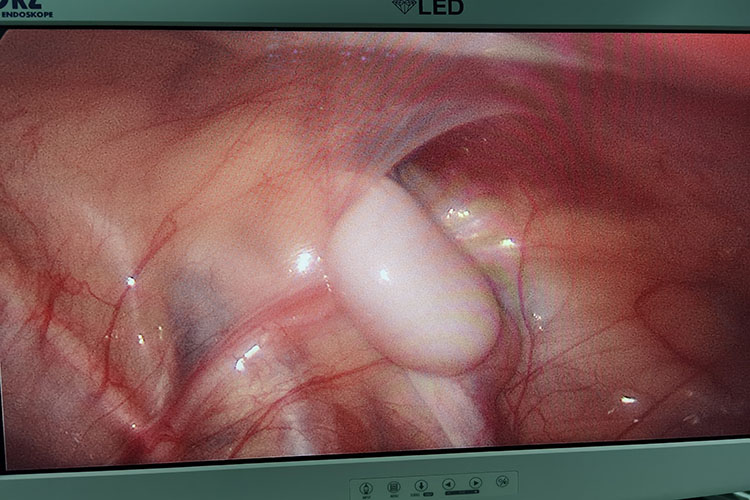

通过腹腔镜检查可以查看到腹腔内存在有隐睾,隐睾CT则表现为圆形软组织肿块,边界清楚,轮廓光整,密度均匀。